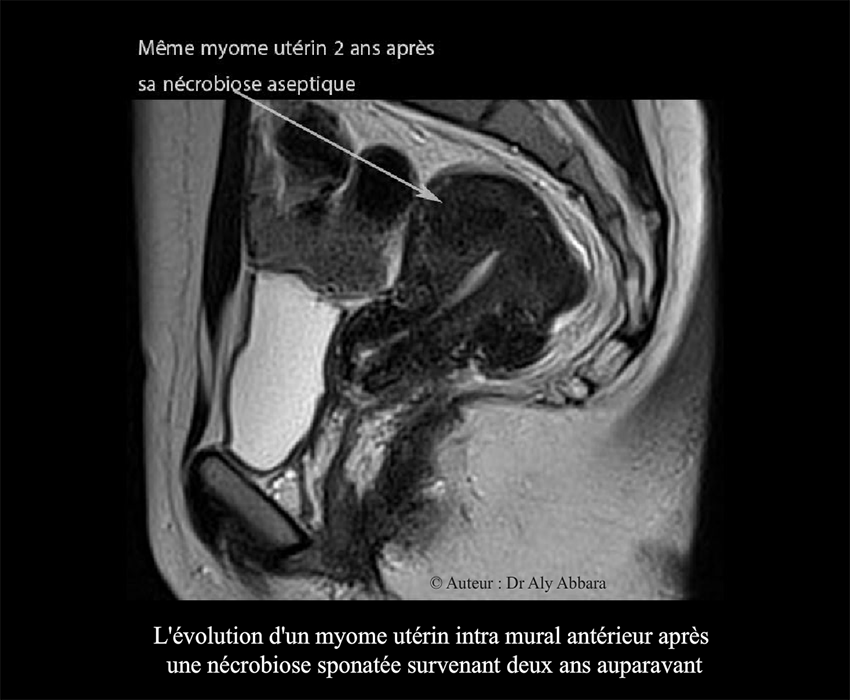

Deux ans après, on observe une réduction spontanée et importante des

dimensions de ce myome : seulement 18 mm de diamètre, soit 3 cm3 de

volume, donc 28,5 fois moins le volume initial.

• Images IRM deux ans après la survenue de la nécrobiose aseptique :

Myome utérin - son aspect après deux de sa nécrobiose aseptique - quasi disparition